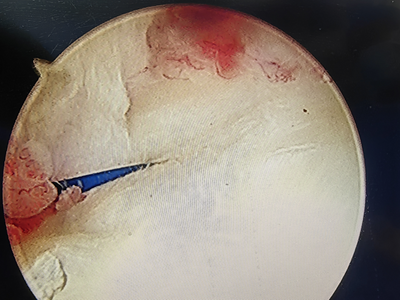

腕关节镜下滑膜清理后,TFCC予以镜下修复